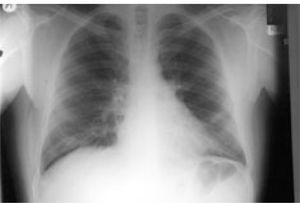

He had positive double stranded anti-DNA (ds-DNA) at 39 RU/mL (normal range: 0-20), positive anti-smooth muscle antibody (ASMA) with titre 1:160 and positive anti-nuclear antibody (ANA) with titre 1:40. His anti-mitochondrial antibodies (AMA) were negative and his Im-munoglobulin G (IgG) was raised only marginally at 17.2 (normal range: 6.0-15.0). A liver biopsy was obtained & showed changes of interface hepatitis with lobular necrosis, cholestasis and pericellular fibrosis while, in the portal tract edges non-caseating granulomas and lymphoid aggregates were present. Due to complaints of chest pain - on a follow-up examination-, a chest radiograph was requested (Figure 1) This x-ray was repeated one month later (Figure 2), while his CT scan findings are shown in figure 3.

LIP is more common in women (average age 55 years) and it has been associated with autoimmune diseases, pulmonary infections, immunodeficiency, serum dysproteinaemias and drug reactions and graft vs host disease (GVHD). Symptoms mostly consist of chronic cough, dyspnoea, weight loss, fatigue and rarely fever while, haemoptysis or chest pain can occur. Few patients (< 4%) are asymptomatic on presentation. Chest x-ray findings include reticular or reticulonodular opacities and to a lesser extend hilar lymphadenopathy, pleural effusions and honeycomb appearance (from extended fibrosis).4,6 High resolution Ctscan images typically show subpleural fibrosis (predominately in basal areas), ground-glass attenuation, traction bronchiectasis and pulmonary parenchymal cysts.3,5